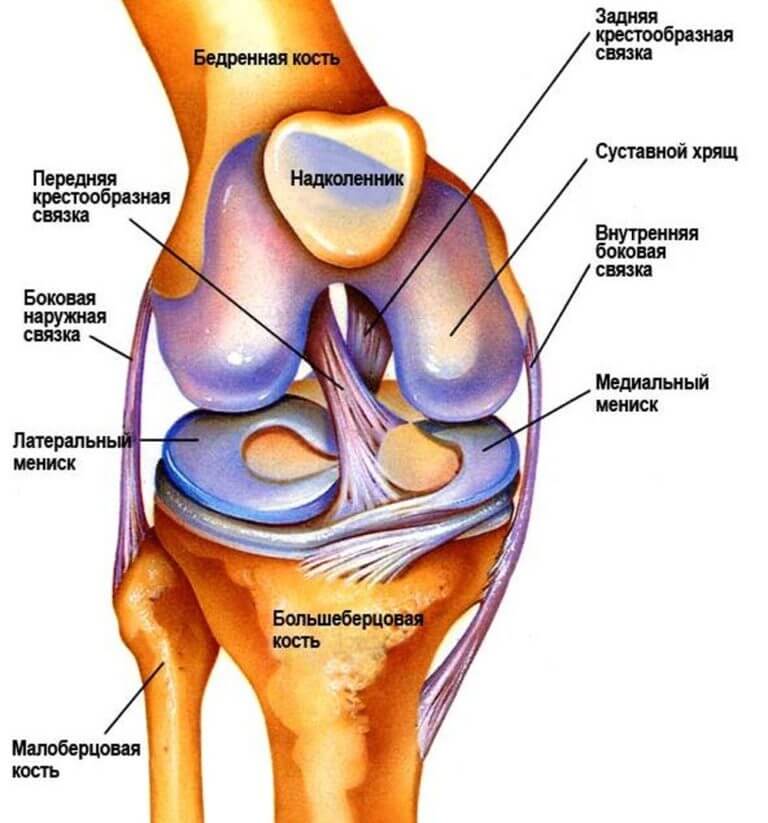

Ежедневно наши колени выдерживают огромные осевые и безосевые нагрузки. Справляться с ними они могут лишь благодаря уникальному строению. Коленные суставы имеют свои анатомические особенности. Изнутри они укреплены крестообразными связками, а между суставными поверхностями формирующих их костей находятся мениски. Подобное строение позволяет коленям справляться с возложенными на них функциями.

Крестовидные связки состоят из соединительной ткани. Они очень плотные и крепкие. Благодаря этому они надежно фиксируют компоненты коленного сустава.

- Крестообразные;

- Боковые,

- Надколенная.

Из всех перечисленных наиболее часто развивается лигаментоз крестообразных связок, что приводит к нарушению полного разгибания, сильной боли, а также ограничения поворота голени при согнутом колене.

- Лигаментоз связки надколенника – при поражении связки, прикрепляющейся к верхней части коленной чашечки, возникают боли в процессе разгибания голени. Объясняется это тем, что эта связка является продолжением сухожилия четырёхглавой мышцы бедра. При хронической форме разогнуть голень невозможно из-за обызвествления связки;

- Лигаментоз боковых связок – порой протекает сочетано с поражением рядом расположенных менисков. Помимо болезненности при движениях пациент ощущает дискомфорт в положении стоя, поскольку мениски – это амортизаторы вертикальных колебаний;

- Лигаментоз крестообразных связок – протекает с острыми болями в нижней части колена, которые усиливаются при выпрямленной ноге. Это объясняется тем, что в такой позиции передняя крестообразная связка напрягается. Вследствие её обызвествления она теряет эластичность и вызывает болезненность. Лечение лигаментоза крестообразных связок коленного сустава весьма затруднительно из-за глубокого их расположения.